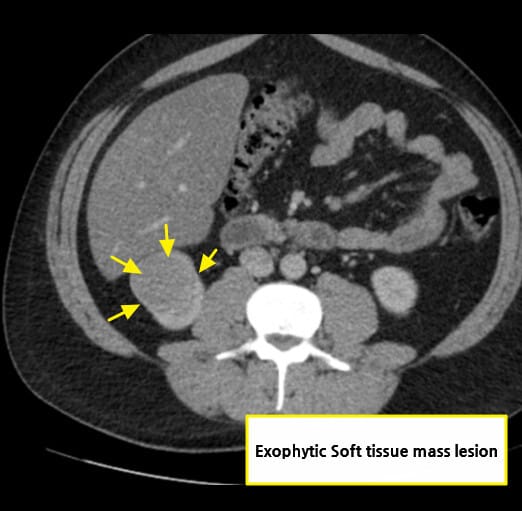

영상소견 정리

CT/ MRI 소견

조영증강 영상에서 고형성 종괴 + 중심 괴사, 혈관 침범

| CT/ MRI 소견 |

| ✅ 조영증강 고형 종괴 |

| CT에서 조영제 주입 시 병변이 비정상적으로 밝게 조영되며, 실질보다 높은 밀도 |

초음파 소견

신세포암(Renal cell carcinoma)은 복부 초음파에서 우연히 발견되는 경우가 많으며, 종괴의 존재 여부와 낭성/고형성 여부를 파악하는 데 유용합니다.

| 🟩 신장 외부 돌출 또는 변형 |

| 종양이 신장 피막을 넘어서 돌출되거나, 신장의 외형이 비정상적으로 변형된 경우 진행된 병기 가능성을 고려합니다. |